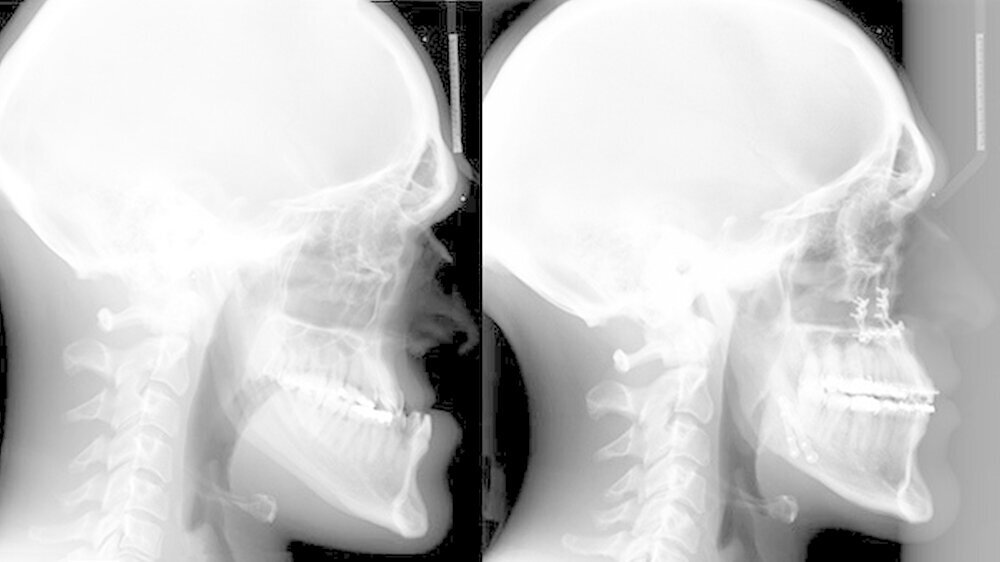

Nach dreidimensionaler Planung im zahntechnischen Labor, in dem die Bissschlüssel konventionell hergestellt wurden, wurden dann ein Jahr später beide Kiefer operativ mobilisiert. Hierzu wurde von einem Schnitt im Mund der Oberkieferknochen freigelegt.

Mit einer Säge wurde ein gezielter Knochenschnitt durchgeführt. Nach der Präparation wurde der zahntragende Abschnitt des Oberkiefers vom restlichen Gesichtsschädel gelöst. Erst wurde die Bisssituation anhand des Bissschlüssels exakt eingestellt, dann mit 2 mm dicken Osteosyntheseplatten aus Titan der Knochen in der neuen Position mithilfe von Titanschrauben fixiert.

Im Unterkiefer erfolgte dann die Schnittführung im Zahnfleisch hinter dem letzten Backenzahn beidseits. Nun wurde der Unterkiefer mit spezieller Technik durchtrennt um die zahntragende Basis vom gelenktragenden Knochenabschnitt des Unterkiefers zu verschieben. Bei der Präparationwurde der im Unterkieferknochen verlaufende Gefühlsnerv der Unterlippe sorgfältig geschont.

Die neue Position wurde mit einem zweiten Bissschlüssel, der die endgültige Bisssituation einstellt,zugeordnet und mit Osteosyntheseplatten und -schrauben gesichert. Die Operation ging mit einem stationären Aufenthalt von nur fünf Tagen einher.

Das deutlich harmonischeres Profil drei Monate nach der Operation: Im Mai des nachfolgenden Jahres wurden die Metallplatten in einem ambulanten Eingriff wieder entfernt. Eine Multibandapparatur hält die Zähne noch "in der Reihe". Der Patient kann heute dank der individuellen innovativen Behandlung ein normales Leben führen, die Gesichtsästhetik und seine Kaufunktion sind vollständig wiederhergestellt.